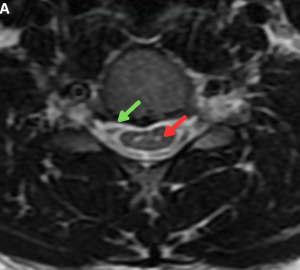

Fig 12: Clinical History: A 29-year-old man presenting with a sudden-onset postural headache.

Figures A and B. Sagittal and axial T2-weighted MR images demonstrating a long-segment T2 hyperintense anterior spinal epidural fluid collection (green arrows).